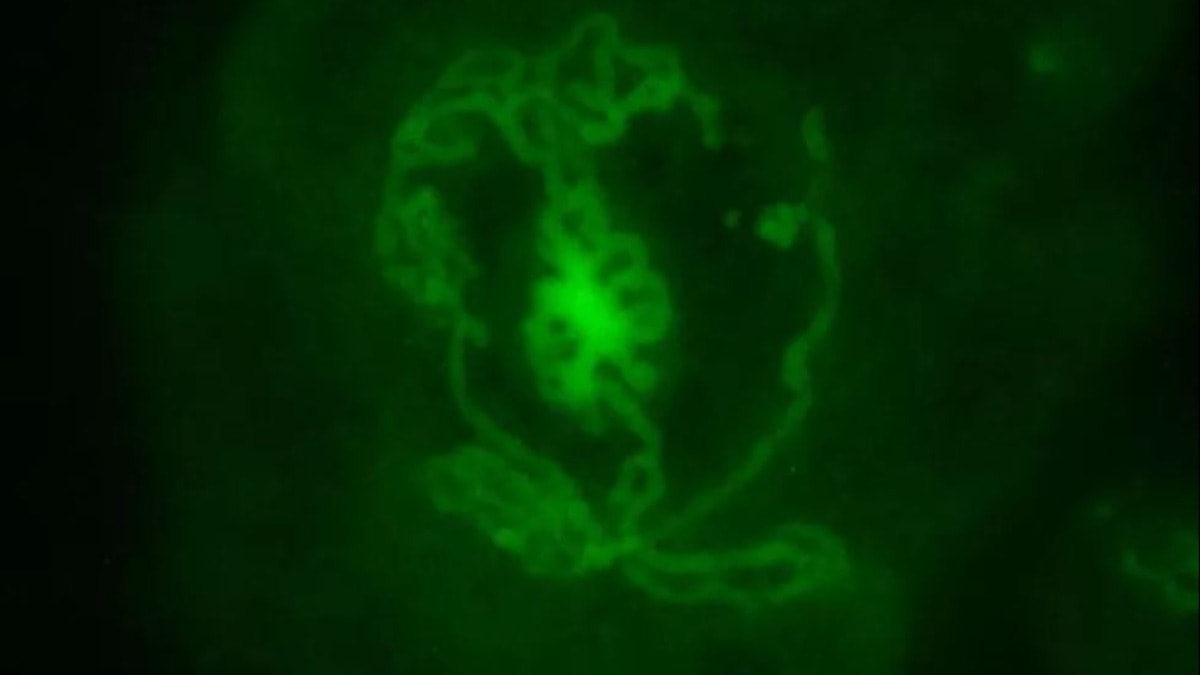

Antibiyotik direncinin önemli bir sorun olduğunu vurgulayan Prof. Dr. Yarsan, “Biz ilacı önerilen dozla, önerilen şekilde kullandık ama neticede bakteri artık antibiyotikten etkilenmez. Bu artık ilaca karşı bir direnç geliştiğiyle ifade edilir. Antibiyotiğe karşı gelişen dirençte en önemli olaylardan bir tanesi dirençli mikroorganizmalardan kaynaklanacak şekilde ölüm oranları son derece yükselmiştir. 2016’da İngiltere’de yapılan bir çalışma var.

O dönemde dünyada yaklaşık 700 bin insanın antibiyotik dirençli mikroorganizmalardan kaynaklanan enfeksiyonlardan öldüğü ifade edilmiştir. Eğer önlem alınmazsa ve böyle giderse 2050 yılında bir yılda ölecek insan sayısı 10 milyon olarak ifade edilmiş. 2024’ün mayıs ayında yayımlanan bir raporda, 2019 yılında bu sayının 1 milyon 200 bin civarında olduğu ifade edilmiş. 2021 yılında ise bu sayının daha da arttığı ve 4 milyon 700 binlerde olduğu söylenmiş” ifadelerini kullandı.

Şu anda her 45 saniyede bir insanın antibiyotik dirençli mikroorganizmalardan kaynaklanan enfeksiyonlar nedeniyle hayatını kaybettiğini kaydeden Prof. Dr. Yarsan, “Eğer önlem alınmazsa 2050 yılında bu rakam her 3 saniyede bir olacak. Bu rakamlar korkutucu ve ürkütücü. Dolayısıyla uygulanacak doz son derece önemlidir. İlacın prospektüsünde belirtilen doz neyse o şekilde kullanılmalı. Antibiyotik direncinde özellikle süre bitmeden ilacın kesilmesi direncin en önemli faktörlerinden biri olarak ifade ediliyor. Ayrıca hekim kontrolünde bu uygulamanın yapılması yine son derece önemlidir” dedi.